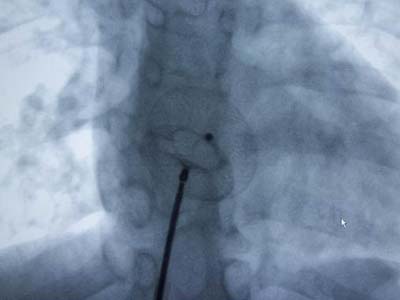

房間隔缺損封堵術(shù)